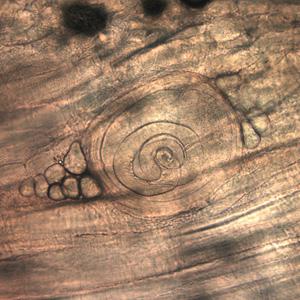

W mięsie znajdują się żywe larwy nicieni, które uwalniane są z cyst pod wpływem soku żołądkowego. Osobniki dojrzewają i rozmnażają się wieloetapowo w przewodzie pokarmowym, skąd drogą krwi trafiają głównie do mięśni. Ok. 20 dnia po zarażeniu larwy które wniknęły do komórek mięśniowych skręcają się spiralnie, tworzą torebkę i mogą pozostać żywe nawet przez kilkanaście lat. Z czasem kompleks ulega reakcji zapalnej, a po dłuższym czasie zwapnieniu.